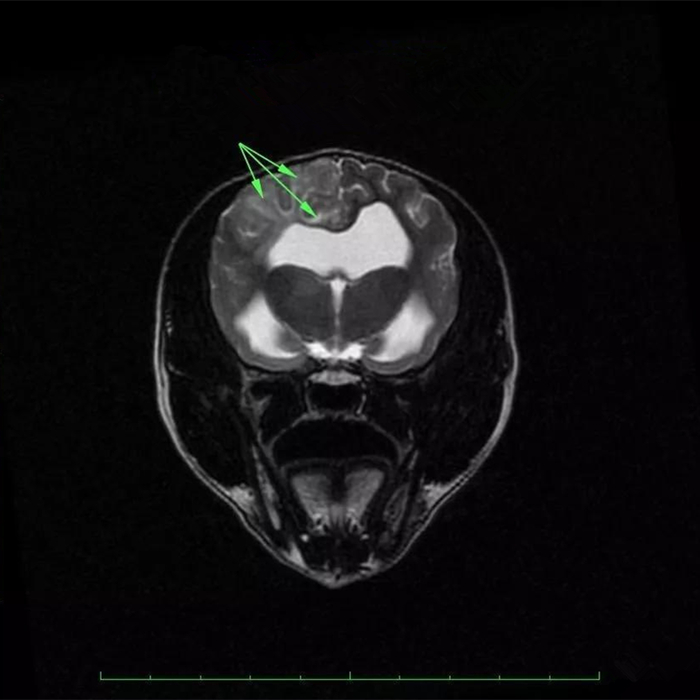

而如果细菌进入狗狗的脑部,会引发一个更严重的疾病,那就是脑膜炎。脑膜炎可以分为化脓性脑膜炎和非化脓性脑膜炎两种,化脓性脑膜炎一般是由头部创伤或者败血症所引起的,而非化脓性脑膜炎则是由传染性细菌或病毒引起的。而因为鼻窦炎所诱发的脑膜炎,自然就属于非化脓性脑膜炎。

狗狗脑膜炎的初期症状为抑郁、体温升高、局部或全身痉挛性抽搐,如果炎症向脑的深处发展,则会引起局部麻痹或全身性麻痹、四肢运动失调、咬肌、咽肌、喉、舌麻痹,最后完全丧失对外反应,造成狗狗的死亡。